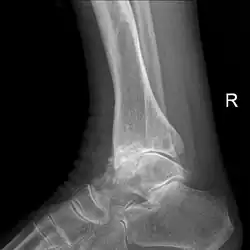

Diagnosis is made with reasonable certainty based on history and clinical examination.[52][53] X-rays may confirm the diagnosis. The typical changes seen on X-ray include: joint space narrowing, subchondral sclerosis (increased bone formation around the joint), subchondral cyst formation, and osteophytes.[54] Plain films may not correlate with the findings on physical examination or with the degree of pain.[55]

Severe osteoarthritis and osteopenia of the carpal joint and 1st carpometacarpal joint